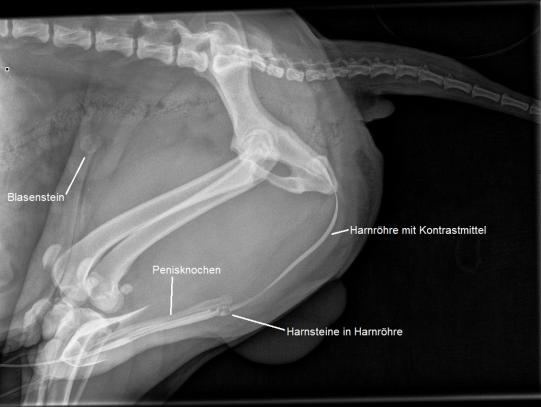

Leider muss davon ausgegangen werden, dass sich der Stein mit den angewendeten Mitteln nicht auflösen lässt und er via Chirurgie entfernt werden muss, um den Hund von dieser chronischen Irritation zu befreien. Der Rüde wird in Narkose gelegt und es wird versucht, ein Harnröhrenkatheter zu legen, um die Blase intraoperativ spülen und die in der Blasenwand gesetze Naht auf ihre Dichtigkeit prüfen zu können. Leider stellt sich heraus, dass ein Katheter von normaler Grösse nicht vorgeschoben werden kann; eine Kathetrisierung lässt sich nur mit einer sehr dünnen Sonde überhaupt bewerkstelligen. Eine Röntgenaufnahme, bei welcher ein Kontrastmittel in die Harnröhre gespritzt wird, bestätigt unsere Befürchtungen: In der Harnröhre befinden sich unmittelbar hinter dem Penisknochen mehrere kleine Blasensteinchen, welche sich dort festgesetzt haben und sich auch mit Druck nicht in die Blase zurückspülen lassen. James Lee wird geweckt, und wir besprechen mit den Besitzern das weitere Vorgehen.